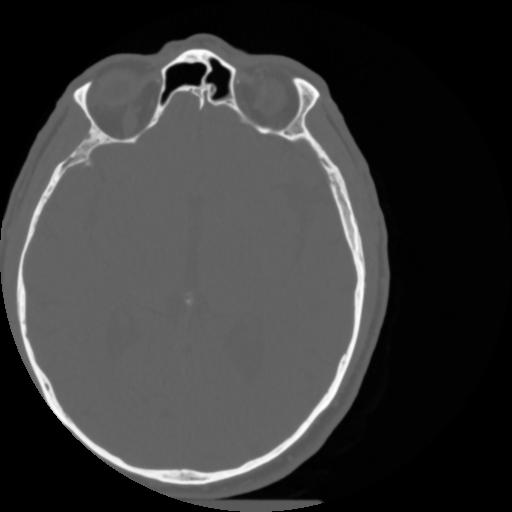

4 CEREBRO,,Vol,0.5,CEREBRO,,